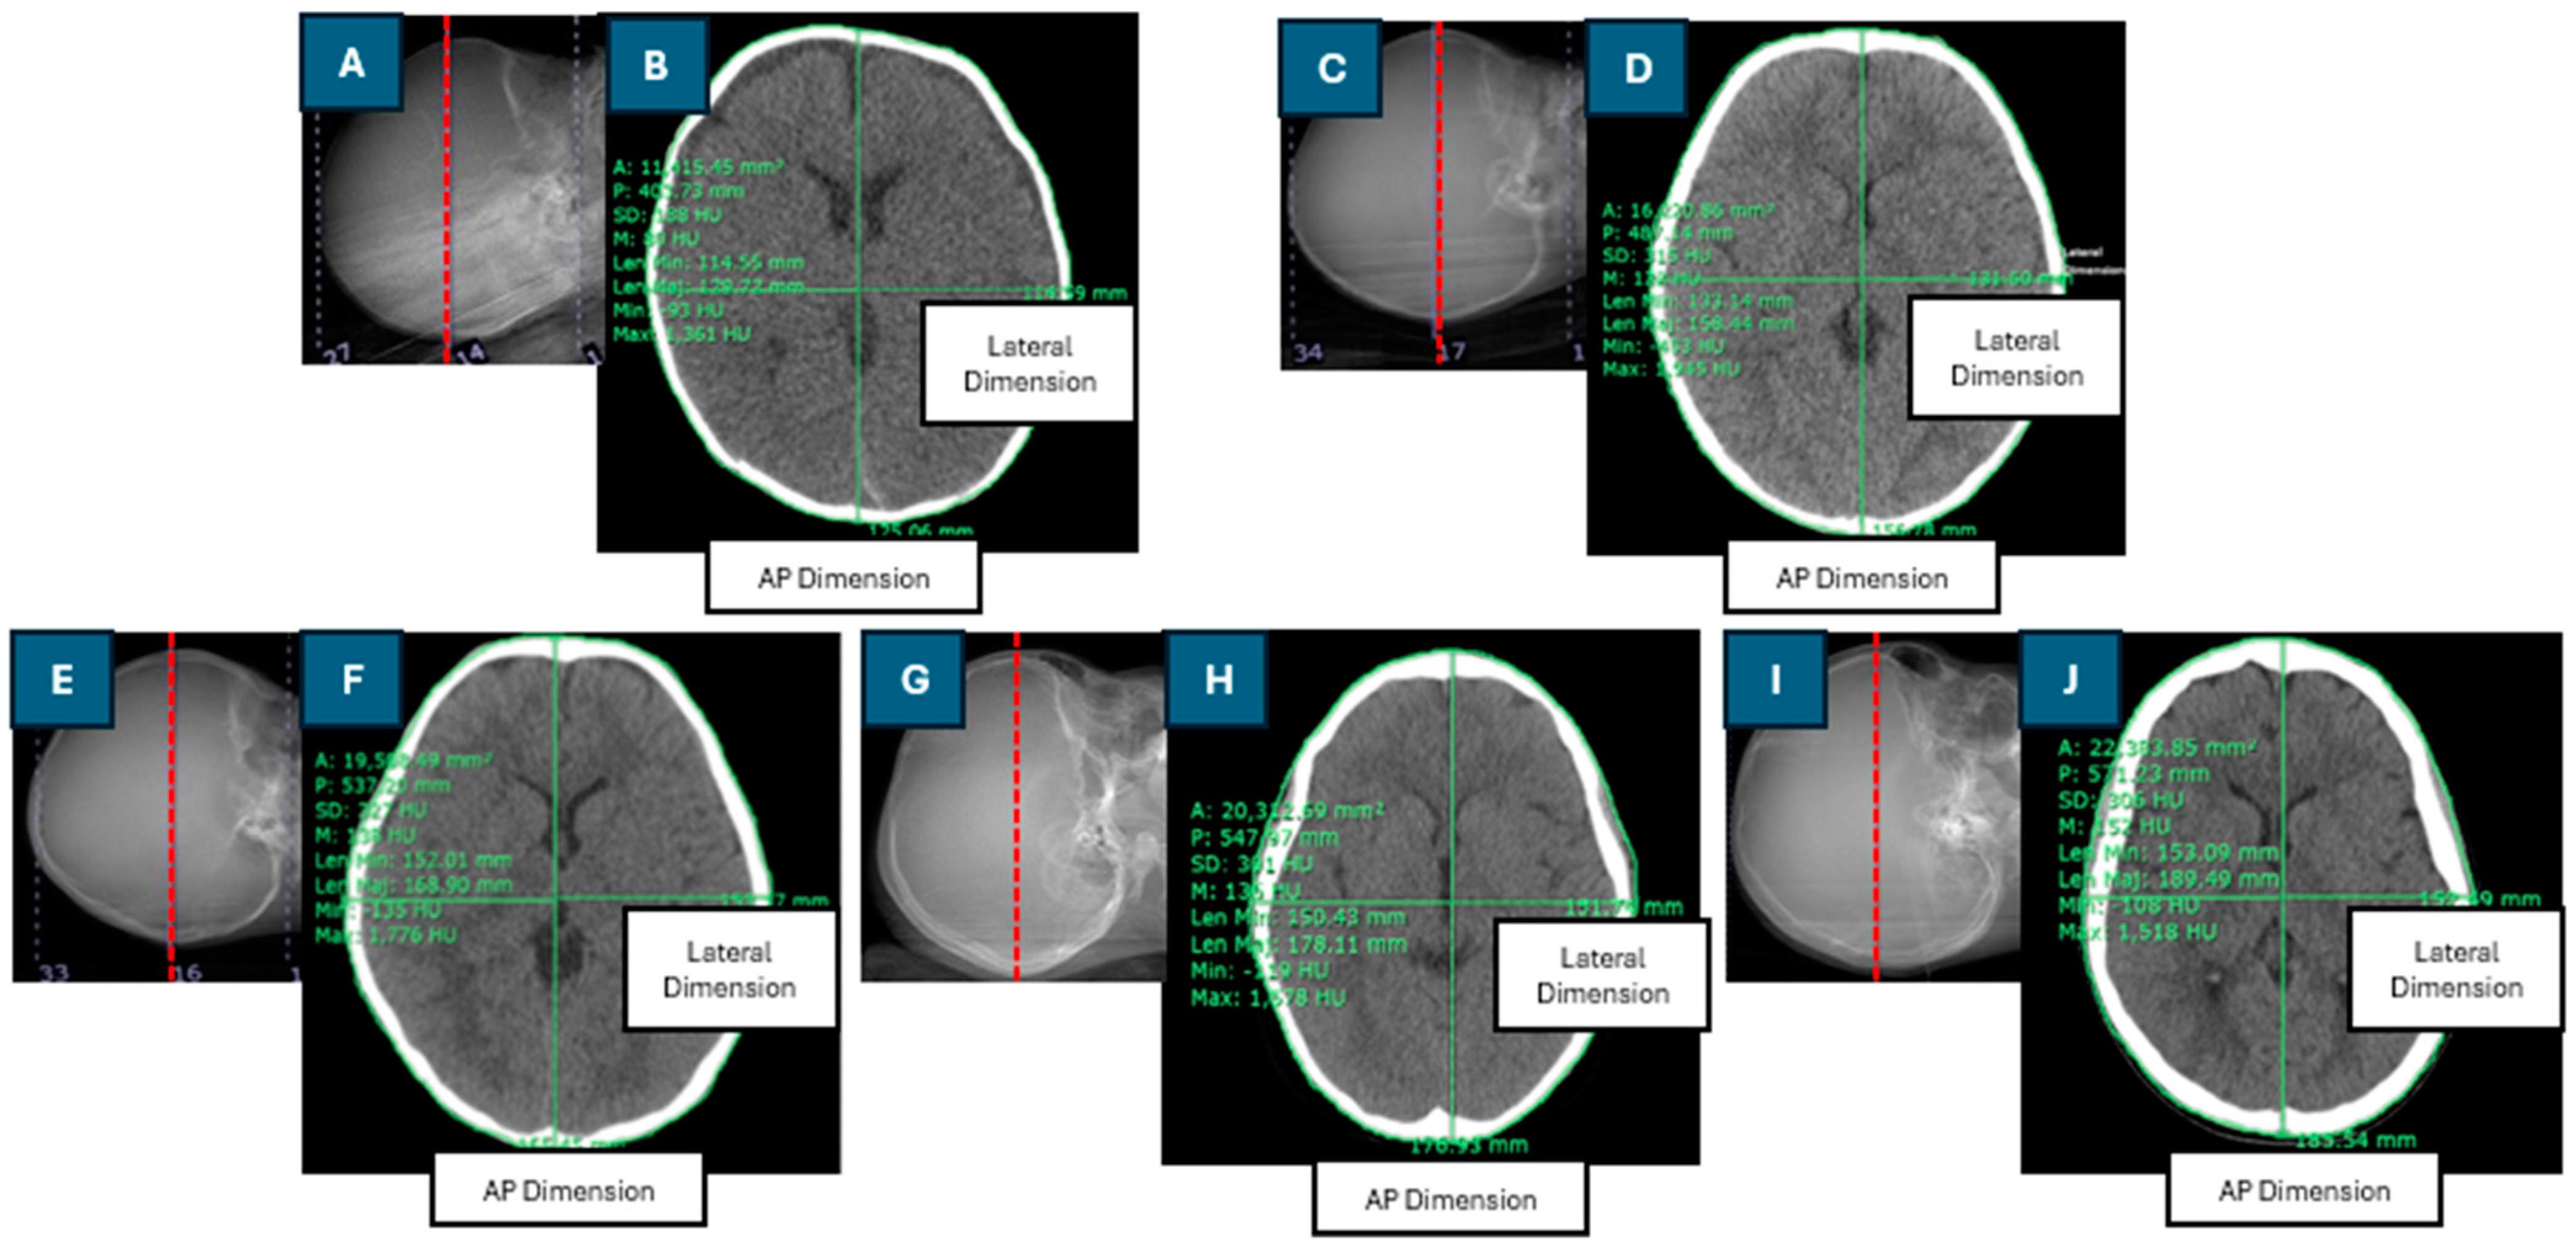

The Dw was calculated using the axial cross-sectional CT image of the brain, selected as the middle slice of the scan length. Patient dimensions and regions of interest (ROIs) were manually drawn using digital calipers and freehand ROI tools within the Synapse software version 4.3.2.1. An ROI was drawn around the perimeter of each patient’s head. The effective diameter (DEff) is the diameter of a circle with an area equivalent to the cross-sectional area of the patient [9]. The DEff was calculated as the square root of the product of the anteroposterior (AP) and lateral (LAT) dimensions. Figure 1 depicts the positioning of the central slice of the scan length in the CT scanogram, the contouring of the region of interest (ROI), and the measurement of anteroposterior (AP) and lateral (LAT) dimensions in the axial cross-sectional CT images for pediatric patients of various ages.

Figure 1.

Positioning of the central slice of the scan length on the CT scanogram and contouring of the region of interest and anteroposterior (AP) and lateral dimensions in the axial cross-sectional CT image in head examinations of pediatric patients of different ages: (A,B): 2-month-old; (C,D): 1-year-old; (E,F): 5-year-old; (G,H): 10-year-old; (I,J): 12-year-old.

In this study, the SSDEDw was estimated for 274 pediatric patients aged 0 to 15 years, and factors influencing the SSDEDw were evaluated. The SSDE based on the water-equivalent diameter (SSDEDW) was calculated using the conversion factor for the CTDIvol to SSDEDW for CT head exams, which was obtained from AAPM Report No. 293. The Dw was derived from the middle slice of the scan length, with the scan region defined as the area extending from the base of the skull to the vertex. The axial cross-sectional CT image from infants and older children encompassed several major components, including brain tissue, the cerebral cortex, ventricles, white matter, gray matter, and skull bones, as illustrated in Figure 1. Each of these components exhibited distinct CT numbers (HU). Additionally, radiation doses, including the CTDIvol, DLP, and organ dose for the brain CT protocol were determined.